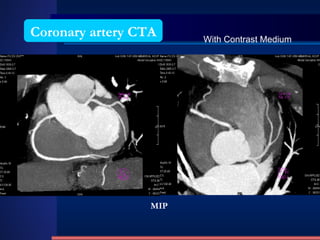

Coronary artery CTA MIP With Contrast Medium

VRT Recon. Normal Coronary artery CTA

Coronary artery CTAMIP With Contrast Medium

VRT Recon. NormalCoronary artery CTA